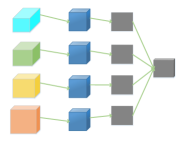

As is well known, it is hard to optimize a deep neural network due to the gradient vanish problem [28]. To alleviate the gradient vanish problem and obtain a good vessel map, we use deep supervision information in the BTS-DSN. Figure 3 gives an illustration of HED, DSN, BS-DSN and BTS-DSN. We can observe that DSN is based on HED except that there are only four side-output layers, and extra hidden layers are added in DSN for better utilizing deep supervision information. When bottom-top short connections are added to DSN, we get BS-DSN. Further, when top-bottom short connection is added to BS-DSN, we get BTS-DSN.

We adopted bottom-top short connections to deliver detail information just as shown in Figure 4. There are three bottom-top short connections in total. Suppose we use VGGNet as backbone. We can observe from Figure 4 that there are four groups of convolution (conv1, conv2, conv3 and conv4) for feature learning in total. We first convolved the last convolution of each group using 16 convolution kernels with size 11. Then, the obtained feature maps are up-sampled 1, 2, 4, 8 respectively to restore to original resolution. Bottom-top short connections are among feat_conv1, feat_conv2, feat_conv3, and feat_conv4.

Let’s take bottom-top short connection between feat_conv1 and feat_conv2 as an example (see Figure 5). The information (feat_1_2) passed from feat_conv1 is concatenated with feat_conv2 to get feat_conv2_fuse. Then, one hand hand, we perform a 11 convolution operation on feat_conv2_fuse to get the information (feat_2_3) delivered to feat_conv3. On the other hand, we performed convolution operation with a kernel size of 11 and sigmoid transformation for feat_conv2_fuse sequentially to obtain the segmentation result (side 2). At last, side 2 is compared with the ground truth to get the loss of the second side-output layer.

2.3 Top-bottom short connection

Bottom-top short connections aim to refine high-level segmentation results. However, we can observe from the first two rows in Figure 1 that the vessel map generated by the first side-output layer contains too many noises while the map generated by the last side-output could capture the main vessel structure. Therefore, we propose delivering high-level structural information to the first side-output layer to reduce its noises. We implemented this kind of information delivery by a top-bottom short connection from conv4 to feat_conv1, which can been seen in Figure 4. We first convolved the last convolution of conv4 using 1 convolution kernels with size 33. Then the obtained feature map are up-sampled 8 to get feat_4_1. The information (feat_4_1) passed from conv4 are concatenated with feat_conv1 to form feat_conv1_fuse (see Figure 5). At last, one hand hand, we perform a 11 convolution operation on feat_conv1_fuse to get the information (feat_1_2) delivered to feat_conv2. On the other hand, we performed convolution operation with a kernel size of 11 and sigmoid transformation for feat_conv1_fuse sequentially to obtain the segmentation result (side 1). At last, side 1 is compared with the ground truth to get the loss of the first side-output layer.